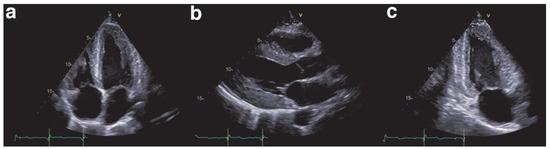

The Eustachian ridge is ablated as part of the cavotricuspid isthmus (CTI) involved in typical atrial flutter (AFL) ablation, but is itself rarely an arrhythmogenic focus. We report a case of a patient with dual tachycardia involving the CTI area....